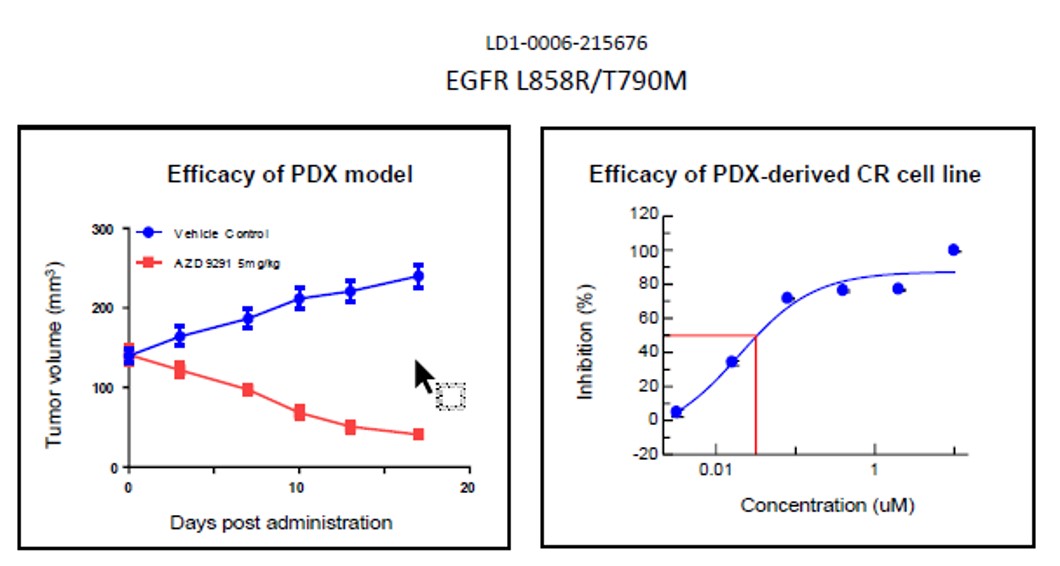

LIDE validated this separately to ensure established CR cells demonstrate heterogeneity like its parental PDX tumors. Below is an example of EFGF mutant PDX models and CR cell lines, showing model drug sensitivities are similar.

Fig. Efficacy results of LD1-0006-215676. IC50 of CR cell line was .03, indicating drug potency

and matching efficacy result of PDX model